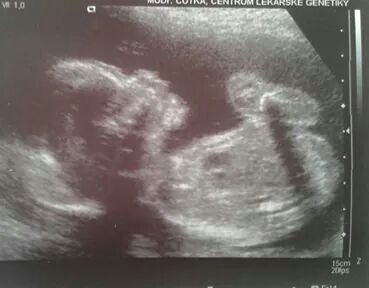

Autor: Pavla   20.8.2014 v 22:13

Ahoj těhulky. Po delší době zase píši,ale vše bedlivě pročítám. Jsem moc ráda,že se všem tak dobře daří. Dnes jsem 21+1 tt a byli jsme s přítelem a s moji maminkou na velkém utz. Utz dopadl výborně,vše je tak jak má být. Potvrdili nám na 100% holčičku. Hambářka pořád roztahovala nožky,tak bylo krásně vidět,že tam opravdu nic neni :D Měří 25cm a váží 325g. Jméno máme vybrané netradiční-Abigail. Dostali jsme i video z utz,tak máme krásnou památku. Přikládám foto naší prdelky z dneška. Všem přeji ať se i nadále daří krásně vám i miminkům :)